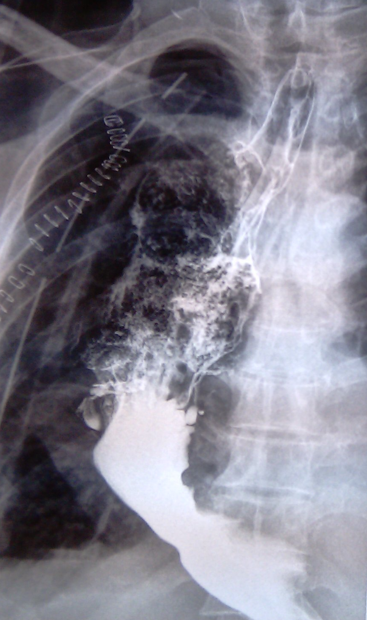

Acid ingestion (HCL). Diffuse burns and contraction/shrinkage of both the esophagus and stomach (Courtesy Dr. V. Penopoulos)